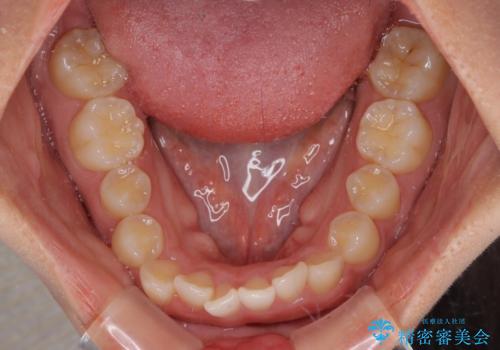

- 前歯の突出感を気にして来院された患者様です。

奥歯の咬み合わせは理想的な咬合に近く、インビザラインでも十分に対応できる歯列でした。

舌の突出癖を改善するためのトレーニングを行いつつ、上下歯列全体を後方に移動させ、更にはIPR(歯と歯の間を削る)によりスペースを獲得することで、口元の突出感を改善することとしました。